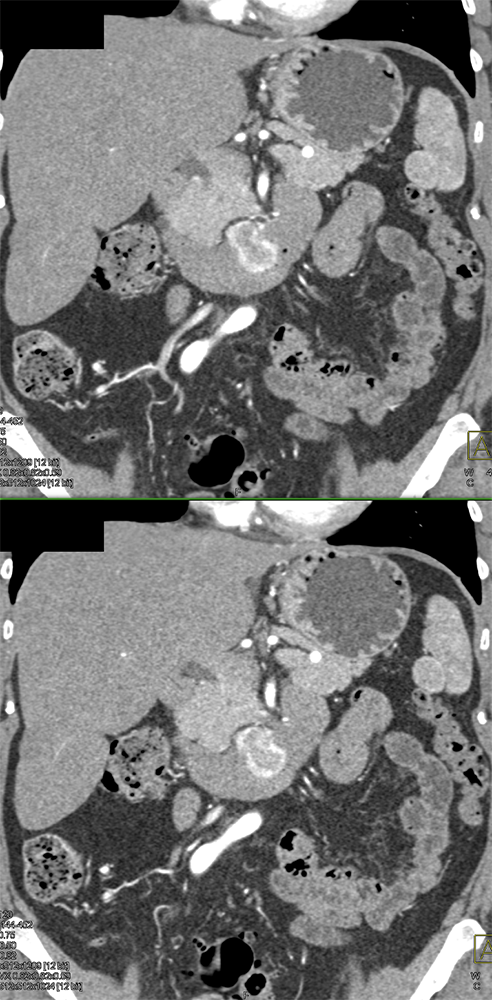

RCC Metastatic to Small Bowel ![]() |

![]() |